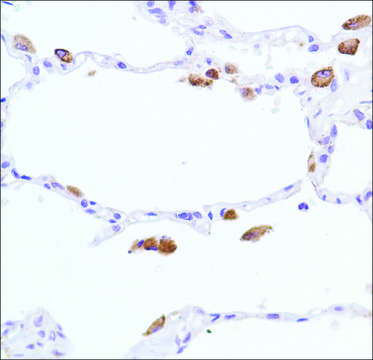

immunohistochemistry: 1:100

Inducible NOS (iNOS) or macrophage NOS (mNOS) is calcium/calmodulin independent and is expressed in activated macrophages and stimulated glial cells. NOS oxidizes a guanidine nitrogen of arginine, releasing nitric oxide in the form of a free radical and citrulline. Nitric oxide thus generated acts as a messenger in diverse functions including vasodilation, neurotransmission, anti-tumor and anti-pathogenic activities.

Synthetic peptide near the C-terminus of mouse iNOS protein.